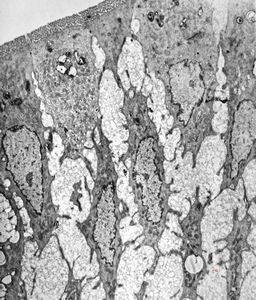

jejunum … lipid malabsorption

duodenum … lipid malabsorption